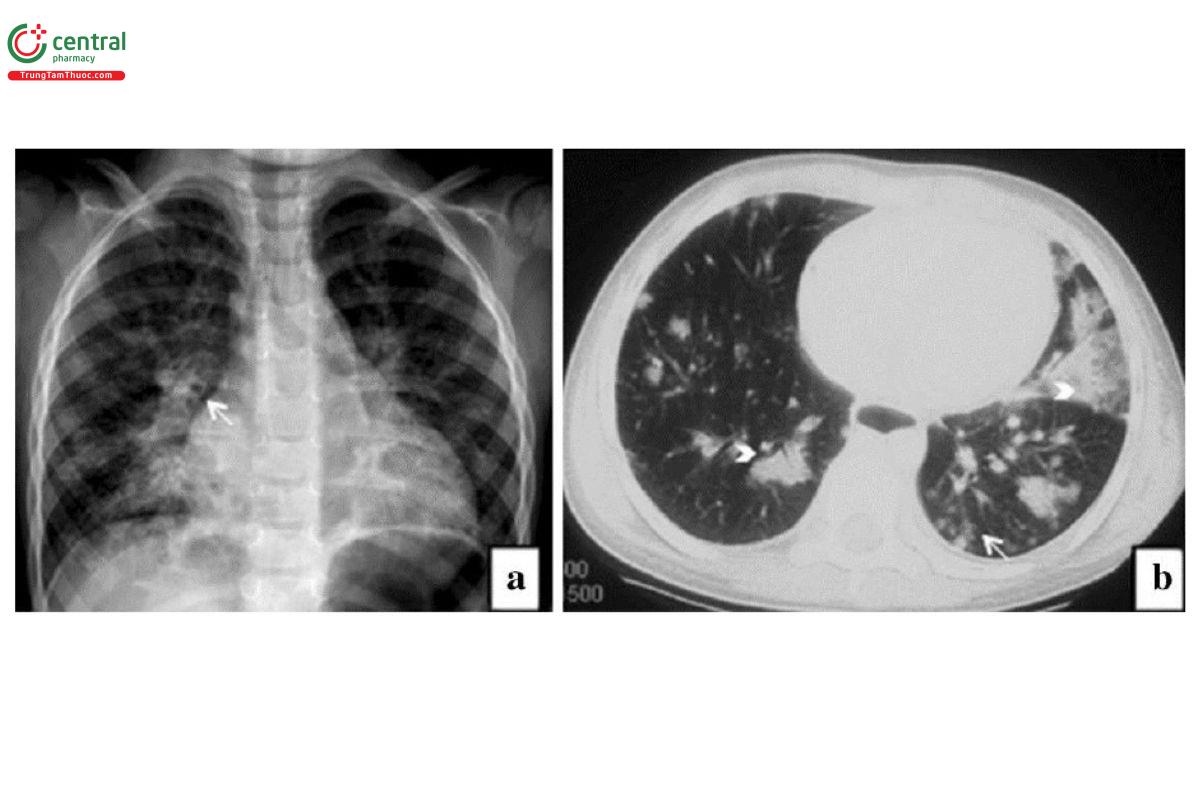

Viêm phổi do Pseudomonas aeruginosa: Hay gặp nhất là hình ảnh viêm phế quản - phổi. Tổn thương ở thùy dưới và hoại tử tạo hang gặp phổ biến.

Chú thích: a) Hình ảnh đông đặc không đều với các nốt trung tâm thùy không rõ ràng và dày thành phế quản (mũi tên trắng). b) Các vùng đông đặc không đều quanh phế quản (đầu mũi tên trắng) và các nốt quanh phế quản ở cả hai phổi (mũi tên trắng)